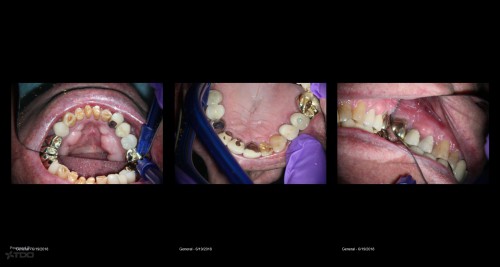

First TDO Outcomes Failure

Collage-2140634438-Page00